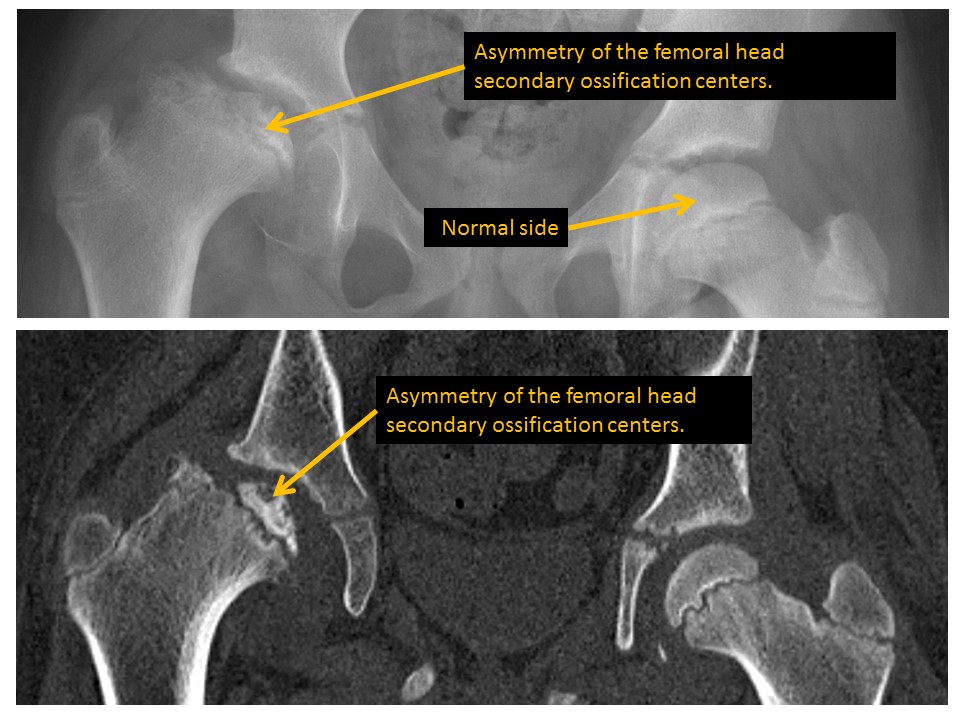

Femoral epiphyseal ossification centers are asymmetric or irregular. [Yes/No]

Femoral physes are asymmetric or abnormally smooth or irregular. [Yes/No]